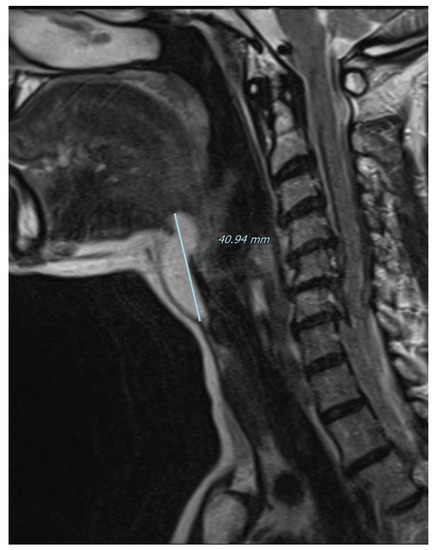

Figure 2.

Computed tomography of the neck on the sagittal plane illustrates the close contact with the hyoid bone whose resection was not necessary in the present case. The 57-year-old woman came to our outpatient clinic because of a slow-growing median cervical swelling that had been present for more than 14 months. She complained of mild neck discomfort without frank dysphagia or dyspnea. Upon physical examination, the subcutaneous swelling was soft and nontender, it was partially mobile on swallowing, and there were no signs of infection or inflammation. Her medical history included seasonal allergic rhinitis, nodular osteoarthritis of the hands, primary Sjogren’s syndrome, and a recent diagnosis of euthyroid Hashimoto’s thyroiditis. There were no known allergies nor she was taking any medication. A full ear, nose, and throat evaluation was uneventful, and the cranial nerves function assessment was normal. In particular, transnasal fiberoptic flexible examination revealed regular oropharyngeal and laryngeal structures with no pooling secretions, and normal swallowing phases for both solids and liquids. In the suspicion of a TGD cyst, an initial ultrasound (US) examination was requested and it revealed a non-cystic hypoechoic mass with scattered hyperechoic spots and a normal-looking thyroid gland; no lymphadenopathies were present. Subsequently, CT and MRI were both ordered in the diagnostic work-up.